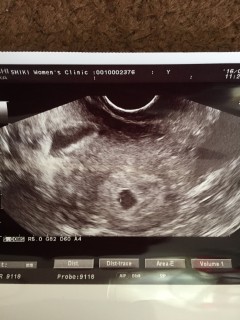

エコーの画面が移った瞬間にすぐにわかりました!胎嚢6.7mmと言われました。 待ちに待った妊娠でとても嬉しかったです!

二人目妊娠。三週くらいからムカムカして生理予定日前日に検査薬で陽性反応。ずーっと下腹部が痛くて不安になり早めの4w4dで病院に行ったけど確認できず、5w0dで確認できました! 6.9mmですっ!でも下の黒い影が出血らしく安静にと言われてしまいました。次は2週間後の心拍確認!無事に大きくなってね!

○エコー写真では端っこにいます。5mmぐらいだねー子宮にも腫れはありませんよ!と先生が仰ってました。7wで出産予定日ももう少し詳しくわかるとの事

生理予定日から1週間、少し早いけど産婦人科受診しました。胎嚢と卵黄嚢は見えるね~と先生。赤ちゃんは、まだ見えないからまた2週間後ね、と。 早く赤ちゃんの心拍確認できますように!